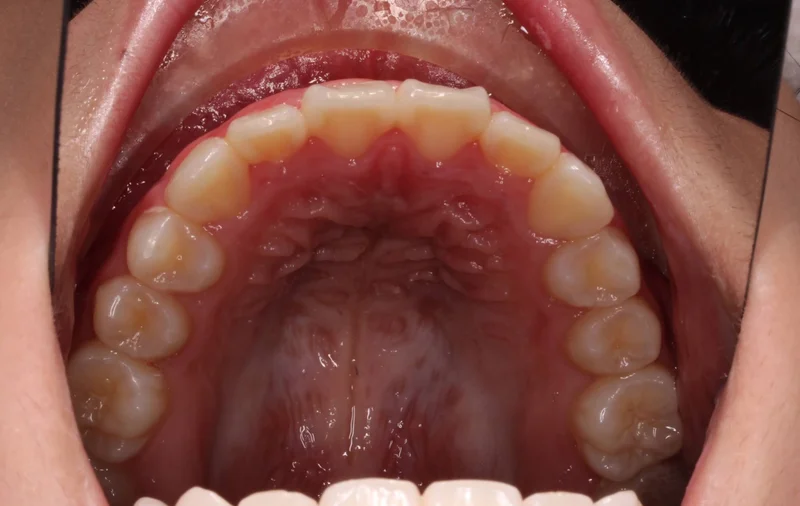

Upper - After Treatment

After